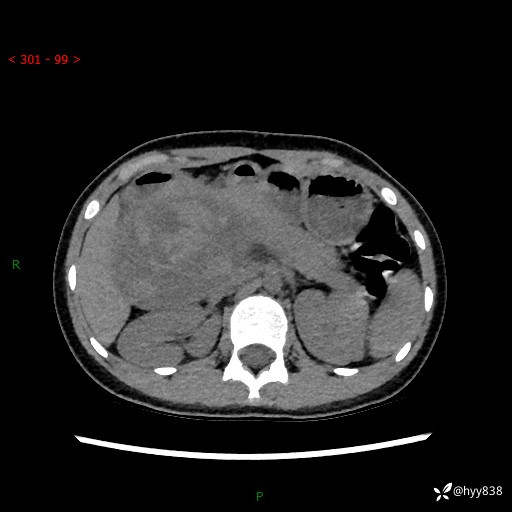

性别:女

年龄:13岁

简要病史:超声提示上腹部巨大包块

上腹部CT平扫